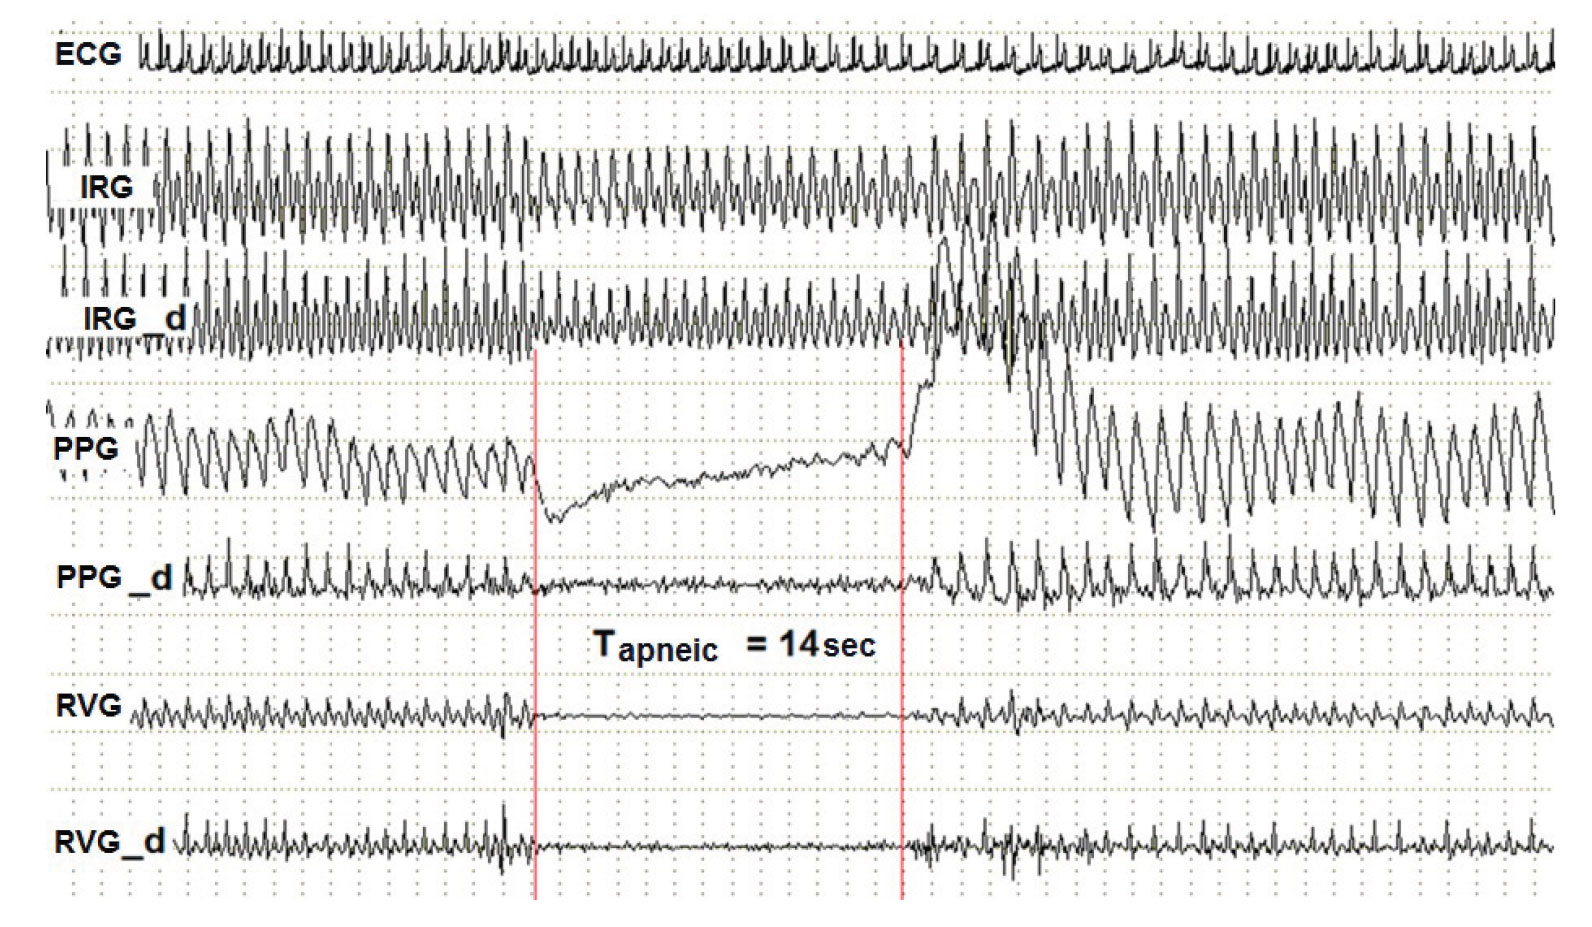

Fig. 1. Dynamics of blood flow when diving on the example of testee I.K.

ECG – electrocardiogram, IRG – integral rheogram, PPG – photoplethysmogram, RVG – rheovasogram, d index – differential of corresponding rheogram, Тapneic – diving time.

Background. The activities of synchronized swimmers are characterized by a number of physiological features that distinguish them from the dry land activities. Water is a powerful irritant of the thermal and tactile skin receptors. Facial and neck skin are particularly sensitive to its effects. When these body parts are submerged in the water, a powerful chain of inherent reflex cardiovascular reactions, the so-called diving reflex, is activated [4]. The diving reflex during submersion is accompanied by the activation of the cold and tactile receptors. From them, on the afferent pathways of the facial and triple nerve, the signals are transmitted to the X pair of the cranial nerves, and from them - to the sinus node of the heart, which results in a reflex decrease of the heart rate, sometimes a decrease in the stroke volume, with a reduction of the minute blood volume. At the same time, the signal is transmitted from the vasomotor center of the oblongata brain through the sympathetic nerve fibers of peripheral vessels, causing the constriction of the skin vessels, inactive muscle vessels, vessels of the gastrointestinal tract and abdominal cavity (see Figure 1).